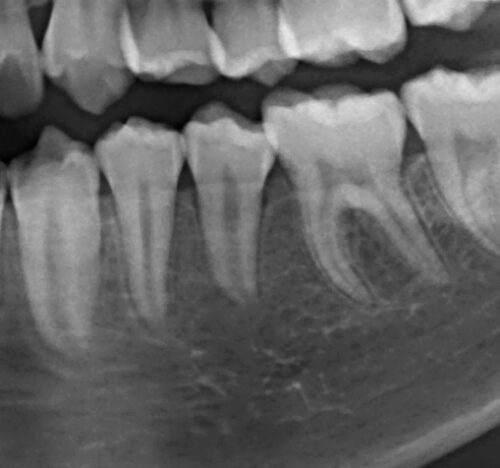

13歳男性、左下5番が萌出不全。エックス線像を見ると両隣在歯に引っかかっており、また歯冠を囲むように嚢胞様の透過像が見られます。

8ヶ月後のレントゲン写真です、しっかりと萌出することができました。